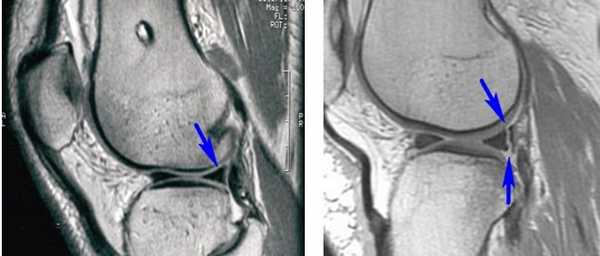

Длительность хирургического вмешательства обычно зависит от степени повреждения мениска. В среднем артроскопия длится 60 минут. В сложных случаях она может продолжаться 1,5-2 часа. На МРТ справа — разрыв заднего рога мениска, слева — здоровый мениск.

При каких диагнозах показана операция - на мениск коленного сустава наложение швов, отсечение разволокненных краев или его полное удаление, внедрение синтетического имплантата? К распространенным проблемам, требующим корригирующей хирургии, относят следующие виды повреждений, подтвержденные результатами МРТ и рентгенографии: